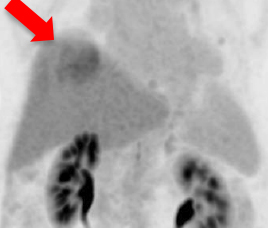

氟18 PSMA正電子/電腦雙融掃描顯示大部分病灶於鑥177 PSMA放射核素治療後可見改善(紅色箭頭所示)。

治療後掃描顯示病灶活躍度大大降低。